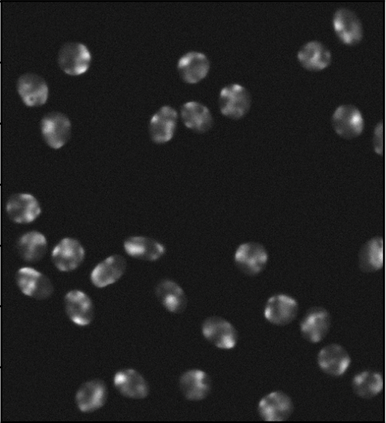

Cell detection in microscopy images is important to study how cells move and interact with their environment. Most recent deep learning-based methods for cell detection use convolutional neural networks (CNNs). However, inspired by the success in other computer vision applications, vision transformers (ViTs) are also used for this purpose. We propose a novel hybrid CNN-ViT model for cell detection in microscopy images to exploit the advantages of both types of deep learning models. We employ an efficient CNN, that was pre-trained on the ImageNet dataset, to extract image features and utilize transfer learning to reduce the amount of required training data. Extracted image features are further processed by a combination of convolutional and transformer layers, so that the convolutional layers can focus on local information and the transformer layers on global information. Our centroid-based cell detection method represents cells as ellipses and is end-to-end trainable. Furthermore, we show that our proposed model can outperform fully convolutional one-stage detectors on four different 2D microscopy datasets. Code is available at: https://github.com/roydenwa/cell-centroid-former